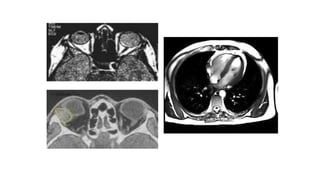

DEFINICIÓN:

• La resonancia magnética nuclear permite obtener

En la cabeza puede ver tumores, abscesos, aneurismas, sangrado,

infartos o lesiones nerviosas. También puede servir para estudiar

patologías en los ojos y en el oído o enfermedades degenerativas

cerebrales.

En el tórax se está utilizando mucho para estudiar la anatomía

cardiaca o la patología de las arterias coronarias. También se utiliza

en el estudio del cáncer de mama o en caso de tumores del

pulmón.

En el abdomen y la pelvis permite estudiar con mucho detalle

órganos tales como el páncreas, los riñones o el hígado, el útero y

los ovarios en mujeres, o la próstata en varones. Allí se pueden

encontrar tumores, infecciones, malformaciones, etcétera.